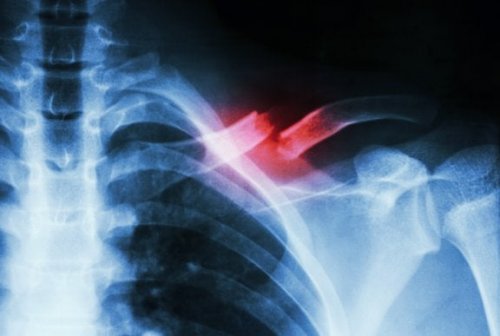

Questo tipo di frattura non è facile da diagnosticare. Richiede l’intervento di uno specialista ed esami complementari per non confonderla con altre patologie. Ciò è anche dovuto al fatto che le radiografie standard spesso non sono in grado di rilevarla.

La frattura si verifica quando s’interrompe la continuità del tessuto osseo. Il più delle volte, avviene a causa di un urto o di un trauma. Nel caso della frattura da stress, le cause del problema sono debolezza e fatica. La debolezza è legata a carenze nel tessuto osseo. Mentre la fatica è legata all’abuso continuo dell’attività muscolare.

La frattura da stress è una sorta di incrinatura dell’osso, che si sviluppa a causa di ripetuti microtraumi o sovraccarichi. Si manifesta soprattutto attraverso un forte dolore, che compare nello svolgimento di attività fisiche e scompare quando si smette.